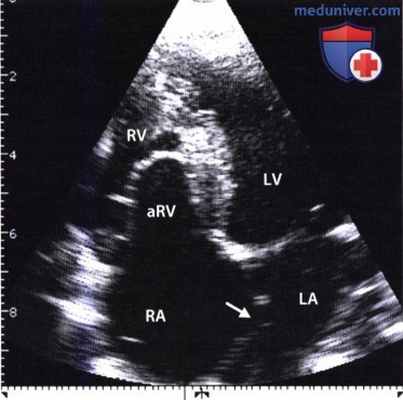

В норме крепление септальных створок митрального и трикуспидального клапана на одном уровне, при аномалии Эбштейна эта дистанция увеличена до 1,4-3,2 см, трикуспидальное отверстие (фиброзное кольцо) сохраняется в нормальной позиции. Смещенные створки трикуспидального клапана в правый желудочек делят его на две части: атриализированную (порция правого желудочка между фиброзным кольцом и смещенными створками) и собственно полость правого желудочка. Порок сочетается со вторичным ДМПП или открытым овальным окном (рис.112).

- Смещение септальной створки в полость правого желудочка в проекции 4-камер с верхушки (более 20 мм у взрослых и 15 мм у детей) (рис.113).

- Наличие атриализированной порции правого желудочка (дистанция между смещенным клапаном и трикуспидальным кольцом).

Тяжелая форма аномалии Эбштейна, выявленная при двумерной ЭхоКГ из апикальной четырехкамерной позиции.

Отчетливо видно смещение к верхушке сердца линии смыкания створок трехстворчатого клапана, связанное с протяженным сращением септальной створки с межжелудочковой перегородкой.

Значительная часть правого желудочка «атриализована» (aRV). На видеозаписи ниже представлена ЭхоКГ больного с легкой клинической формой аномалии Эбштейна.